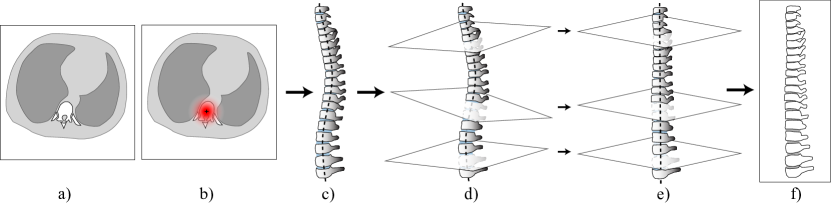

Refer to caption

Figure 1: Overview of the proposed model. Step 1: a) localizing vertebrae centers in 3D CT (a sagittal projection is shown); b) generating a new 2D image via spine ‘straightening’. Step 2: c) identifying key-points and the corresponding heights; d-e) a closer look at some vertebrae (colors denote the fracture severity). Finally: f) the original image with estimated fracture severities.

Our contribution is two-fold. First, we propose a new method to identify the vertebral column in 3D CT and, as a consequence, reducing the problem to 2D by producing the corresponding mid-sagittal slice [4] to measure ha,hm,hpsubscript𝑎subscript𝑚subscript𝑝h_{a},h_{m},h_{p} for each vertebra (Fig. 1a,b). Our method is trained to directly solve the localization problem rather than spine segmentation and demonstrates excellent localization quality with the average error less than 111 mm. Also, it allows us to process all studies with no exceptions, including cases with severe scoliosis. Second, our method estimates six keypoints to detect each vertebra and estimate its heights hsubscripth_{*} simultaneously (Fig. 1c-e), which results in excellent fracture classification quality with the area under ROC curve equal to 0.930.930.93. The predictions are highly interpretable as they can be validated by a doctor using a simple ruler.

By combining the predictions for each axial plane, we obtain a 3D curve. We then interpolate the image onto a new 3D grid on which the obtained curve becomes a straight vertical line. The grid is constructed in such a way, so that the planes normal to the curve become parallel (Fig. 2d-e). Finally we select a new sagittal plane where all vertebrae are visible. Fig. 2 shows a detailed illustration.

Fig. 1 shows an example of the inference process on an image from the dataset. Due to limited space, we refer the interested reader to the supplementary materials for a broader set of examples. The overall inference takes under 222 seconds on Nvidia GTX 980ti, with an approximately equal time required for spine localization and all the subsequent steps (including spine straightening).